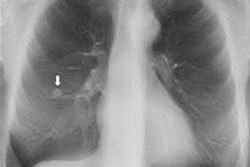

Much of the recent research on digital chest tomosynthesis has focused on the technology playing an intermediary role between chest radiography and CT. Conventional radiography has notoriously poor sensitivity for lung nodules, leaving many patients to be sent on to CT, where suspicious lesions are often found to be benign. Could tomo help resolve some of these cases?

Mining the hospital's PACS database for tomosynthesis cases revealed 149 patients who had received tomosynthesis exams in March 2010 after suspicious nodules were detected on conventional chest x-rays. This particular time period was selected because by then clinical use of tomosynthesis at Sahlgrenska University Hospital had stabilized. It also enabled the acquisition of follow-up data in the three years between the study period and when the paper was written.